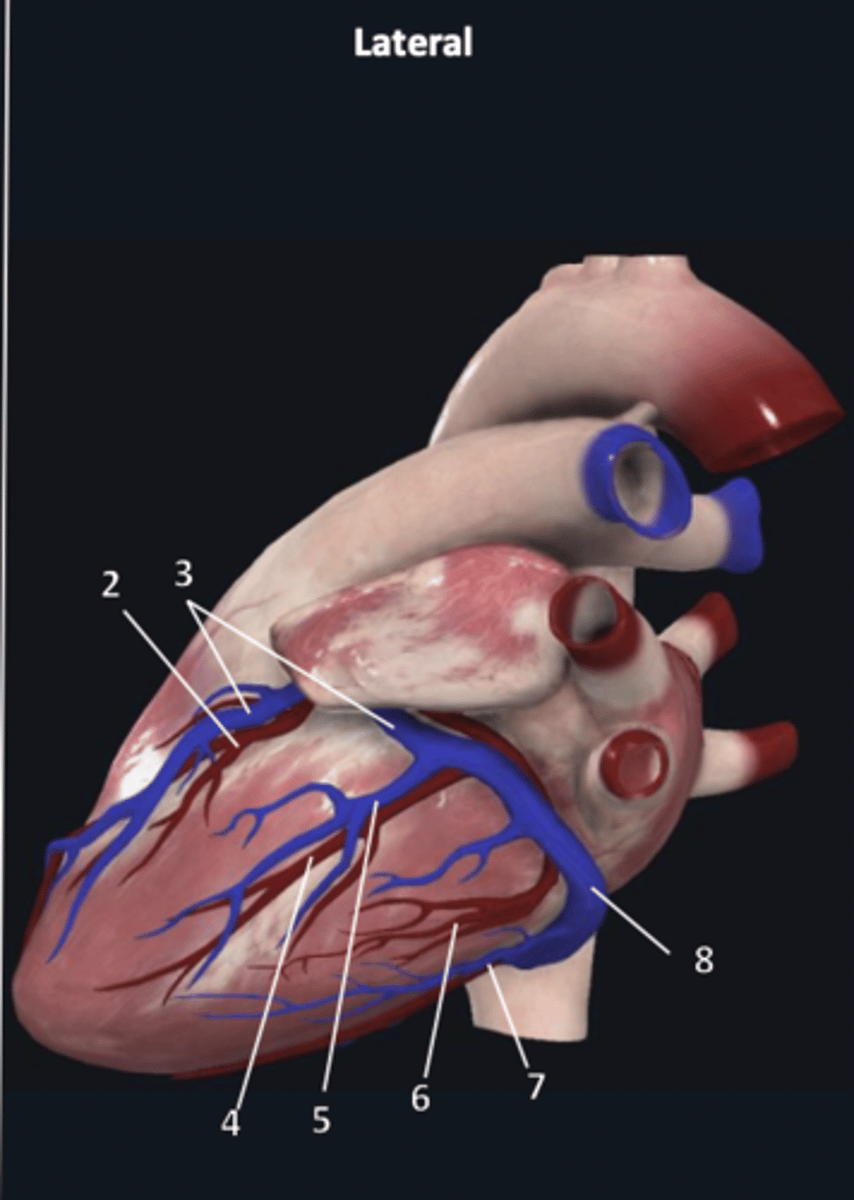

right coronary artery

1

anterior interventricular artery

2 (red)

great cardiac vein

3 (blue)

anterior interventricular artery

2 (red)

great cardiac vein

3 (blue)

left marginal artery

4

left marginal vein

5

posterior left ventricular artery

6

posterior vein of left ventricle

7

coronary sinus

8